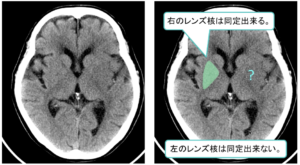

| ② | ②レンズ核輪郭の不鮮明化(=高吸収域の消失)が発症後1~2時間で出現![]() |

| ③ | ③皮髄境界・島皮質の不鮮明化といった浮腫性変化が発症後2~3時間で出現![]() ![]() |